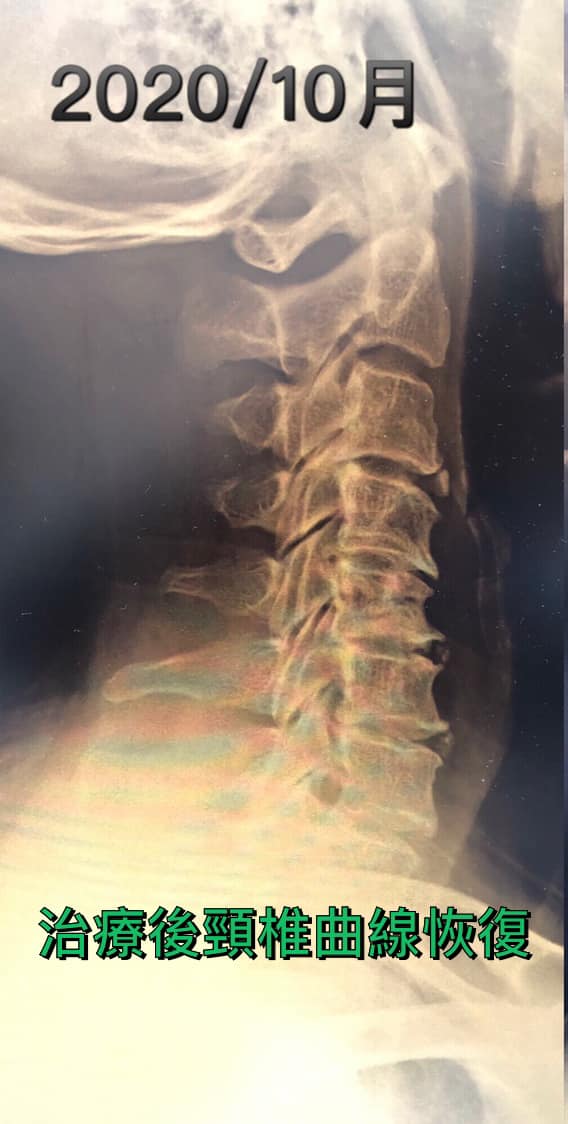

臨床上很多頸椎病的個案頸椎的正常前凸曲線都已經消失,嚴重者甚至是有反弓的曲線!就如個案約五十多歲,男性,有非常典型的肩頸痠痛之外,也伴隨上肢抽痠麻、頭痛、暈眩、喉嚨有異物感,時間快一年,最近幾個月嚴重惡化。

看了他的X光片就知道他的頸椎嚴重變形,已經到反弓的現象,正常頸椎的前凸生理曲線可以幫助頸椎吸收由下肢行走時傳導至頭部的力道,漂亮的弧線是天然的避震系統,他頸椎已經產生「走山」現象 ,頸椎的關節與椎間盤承受過度的壓力,頸椎周邊的肌肉也會因為曲線的消失,而容易變得緊繃,最終導致椎間盤突出壓迫神經根與脊髓!

患者非常認真的接受微針減壓療法 更重要的是他卯起來做毛巾操跟收下巴運動,每天超過五百次以上,堅持了兩個多月,看到令人感動的片子,可以說頸椎反弓現象消失了,當然患者臨床症狀也改善很多。

心得:微針刀減壓搭配毛巾操強化肌肉,將骨頭拉回去正常位置,把椎管打開,才有可能徹底改善,否則錯誤姿勢就算做完手術還是會復發